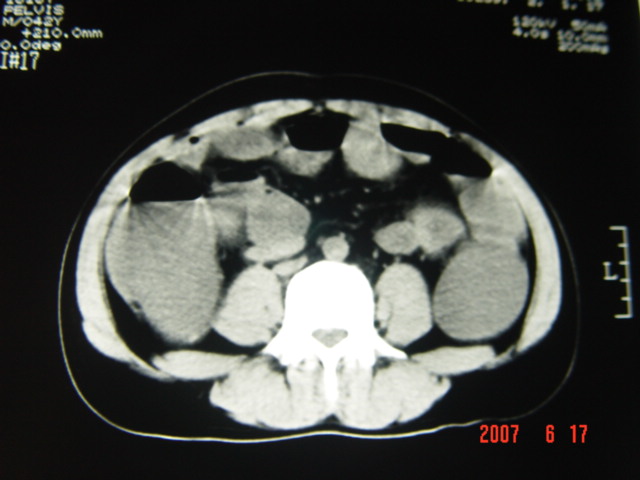

[br][br]以下是引用lkc8963在2007-6-17 13:32:00的发言:[br]完全支持邓主任意见:降/乙交界部占位性病变伴不全梗阻.做个增强或者be可能更好.